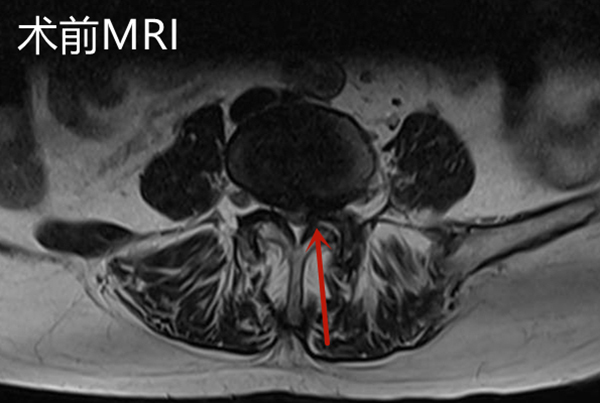

邱奶奶入院后查腰椎磁共振顯示L4/5椎管嚴重狹窄,神經根受壓,明確診斷為腰椎管狹窄癥。腰椎骨狹窄癥是老年人群常見的腰椎退行性疾病。狹窄可以發生在中央椎管、側隱窩以及椎間孔等部位,由于椎管或神經根管的狹窄,致使椎管內神經受壓,神經功能障礙,可表現為腰痛、下肢疼痛或麻木,隨著病情的發展可出現下肢運動及感覺障礙。

手術后復查腰椎MRI顯示:相應的椎管狹窄及神經根壓迫已解除,手術后第2天邱奶奶便可下地行走,腰痛及左下肢疼痛緩解,復查腰椎磁共振見L4/5左側狹窄已完全解除。手術后第4天,患者順利出院,沒有出現任何手術并發癥。